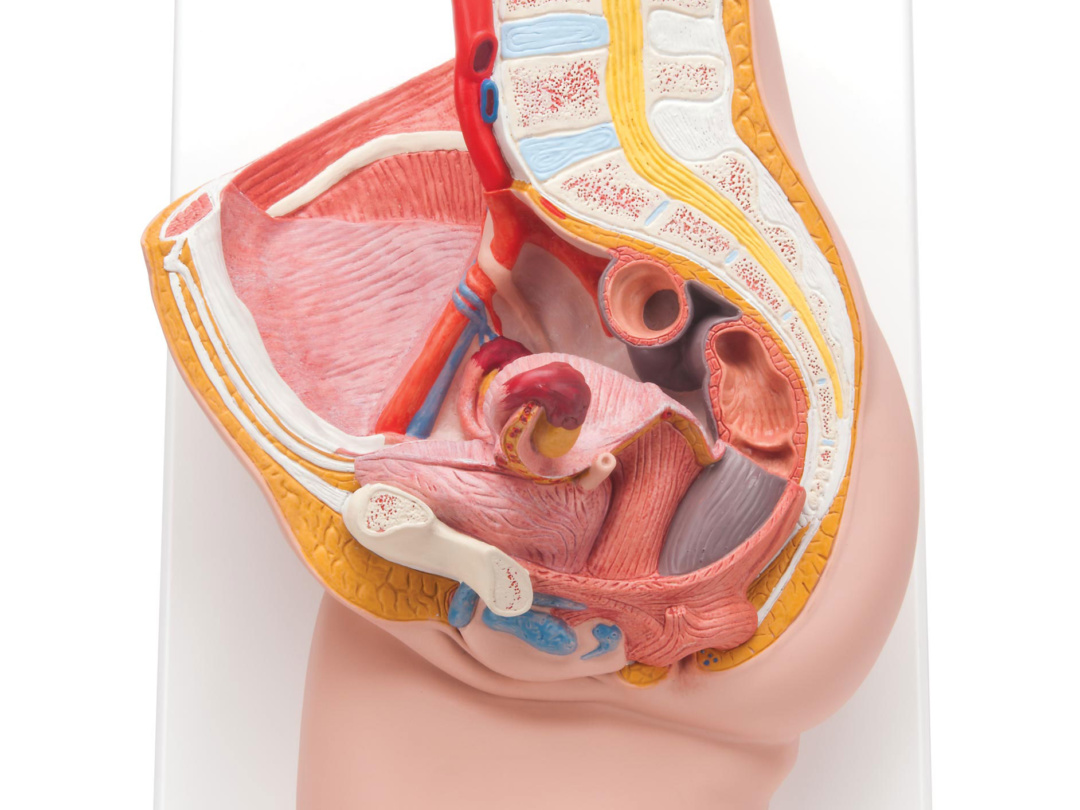

H10 女性骨盤内臓器 2分解モデル Medimann メディマン タカチホメディカル株式会社

女性骨盤内臓器 2分解モデル ボード型 日本スリービー サイエンティフィック

女性骨盤 内臓 骨盤底筋付 6分解モデル 日本スリービー サイエンティフィック

女性骨盤 内臓 骨盤底筋付 6分解モデル 日本スリービー サイエンティフィック